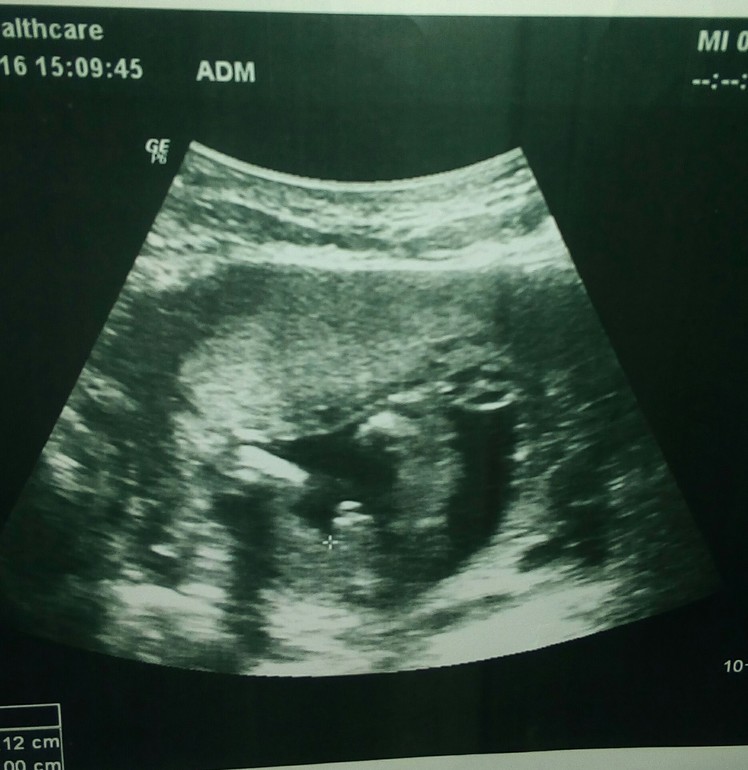

сыночек,срок 14 недель